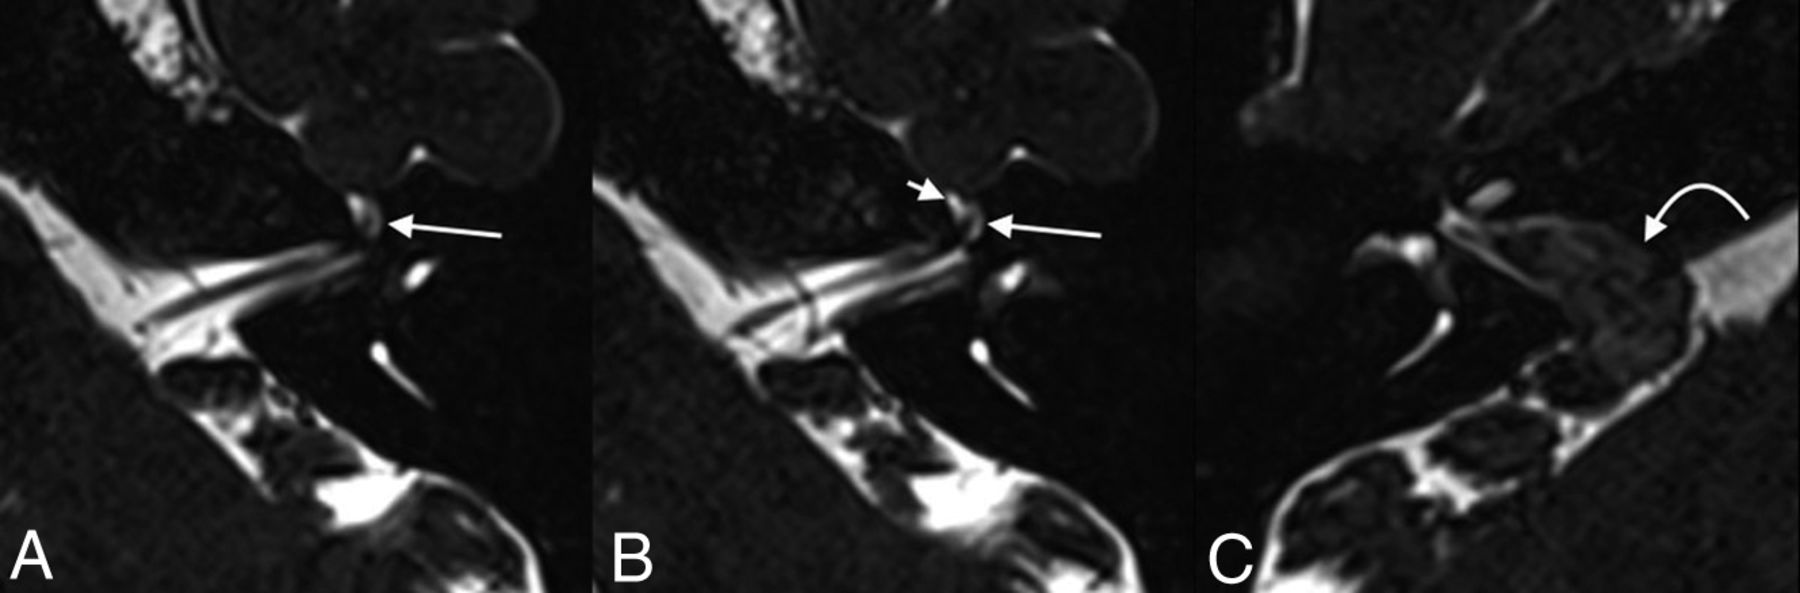

A 55-year-old woman who presented with persistent dizziness. From inferior to superior, axial T2 SPACE images demonstrate fluid-filled remodeling/expansion of the right geniculate ganglion fossa (straight arrows), compatible with a meningocele (A–C). The labyrinthine segment of the facial nerve canal (curved arrow) is 0.9 mm in diameter, which is at the upper limit of normal but does not meet the defined size criteria for a meningocele. The normal left side is shown for comparison (D).